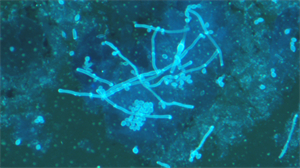

广西自贸区医院于2025年引入广州明慧公司UB203i-FL荧光显微镜,专用于真菌荧光染色观察,解决了传统染色方法灵敏度低、成像模糊的难题。该设备通过高亮度荧光照明系统和精密滤光片技术,确保激发光线精准匹配真菌特异染料,显著提升图像分辨率与对比度,使细长病原体结构在显微镜下清晰可见,有效减少漏诊风险。

精准成像优化诊断:UB203i-FL专为真菌荧光设计,通过紫外(330-385nm)、蓝色(450-490nm)等多波段激发光系统,精确分离荧光信号,捕获细胞壁特征,成像效果满足临床微生物荧光检测要求。